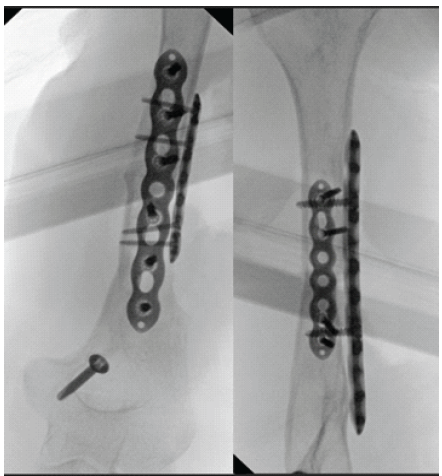

The shaft was then preliminarily fixed with a 2.7 mm plate and arm rotation was checked. A second, 3.5 mm plate was then added for further stability (Fig. 4).

Figure 4: Intraoperative anteroposterior and lateral fluoroscopy of the humeral non-union fixation; intraoperative anteroposterior and lateral fluoroscopic images of the humeral non-union after fixation and grafting.